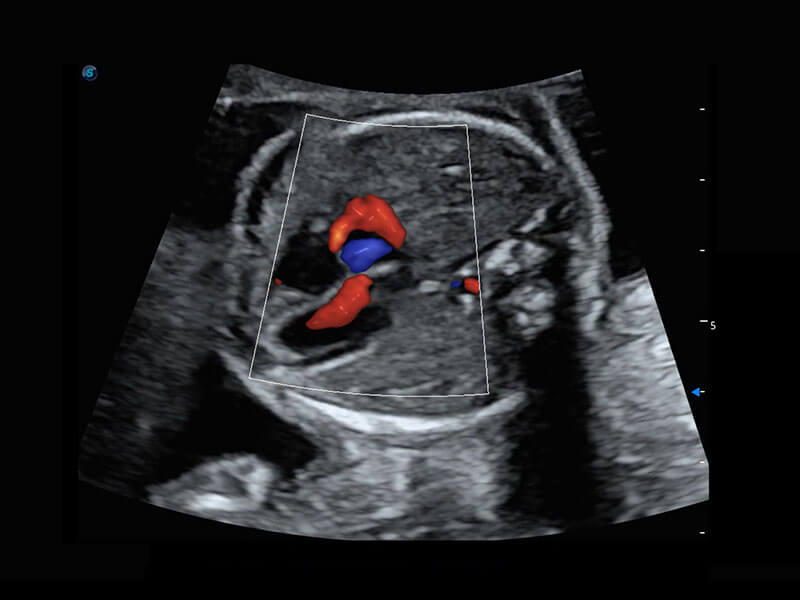

P60在胎儿早孕期超声筛查中为您带来优异的图像质量。

早孕-胎心

高分辨率容积成像-早孕胎儿

胎儿体循环

光影成像-孕囊